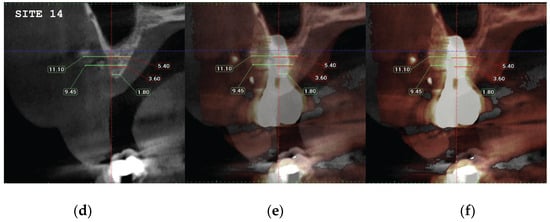

| CASE1-14 | 1 mm | 0 | 1.80 |

| 3 mm | 3.60 | 9.45 | |

| 5 mm | 5.40 | 11.10 | |